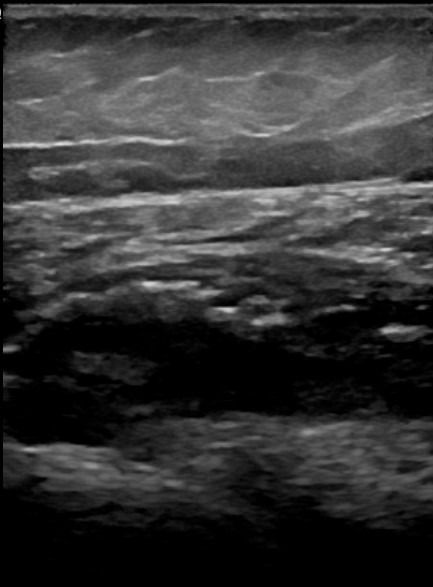

- Τενοντοπάθεια ή ρήξη γλουτιαίων τενόντων, ορθού μηριαίου και οπίσθιου μηριαίου

- Τροχαντηρίτιδα: συλλογή υγρού στους θυλάκους των γλουτιαίων τενόντων στο μείζονα τροχαντήρα